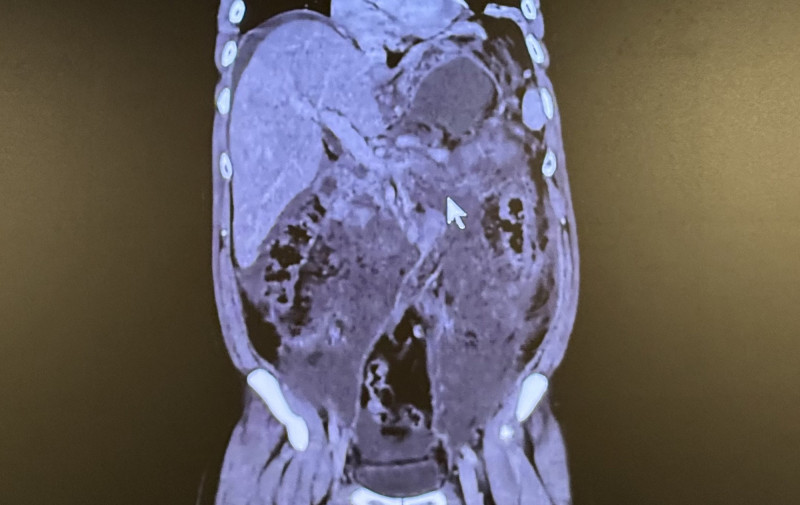

39歲男誤當胃脹氣!竟是「壞死性胰臟炎」 死亡率達6成

急性胰臟炎為臨床常見且進展快速的急症,台灣每年平均約每10萬人有37人發生,其中約70%與膽結石有關,20%的病人可能惡化為壞死性胰臟炎,一旦合併感染與多重器官衰竭,死亡...…